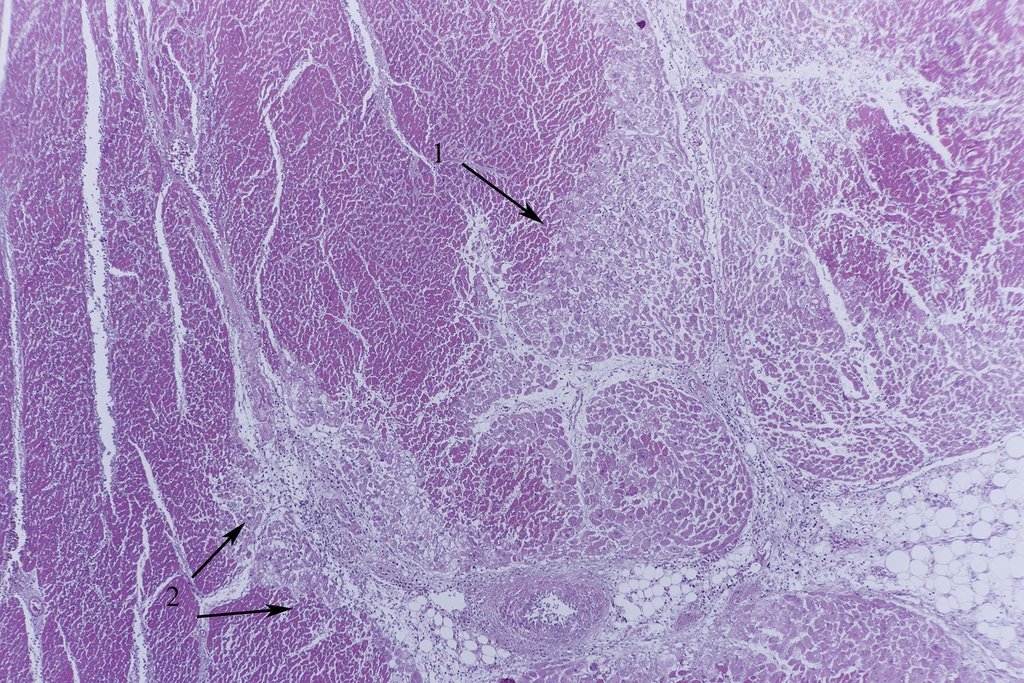

Bild 3 ist eine Übersicht eines Infarktes und man erkennt schon Unterschiede

in der HE Färbung. In der Vergrößerung wird man bei 1 einen deutlichen

Verlust der Herzmuskelfaserstruktur mit Hypereosinophilie und Verlust der

Querstreifung und der Zellkerne finden, und bei 2 eine Einwanderung von

Entzündungszellen (Bild 4 und 5, Paraffin, HE).